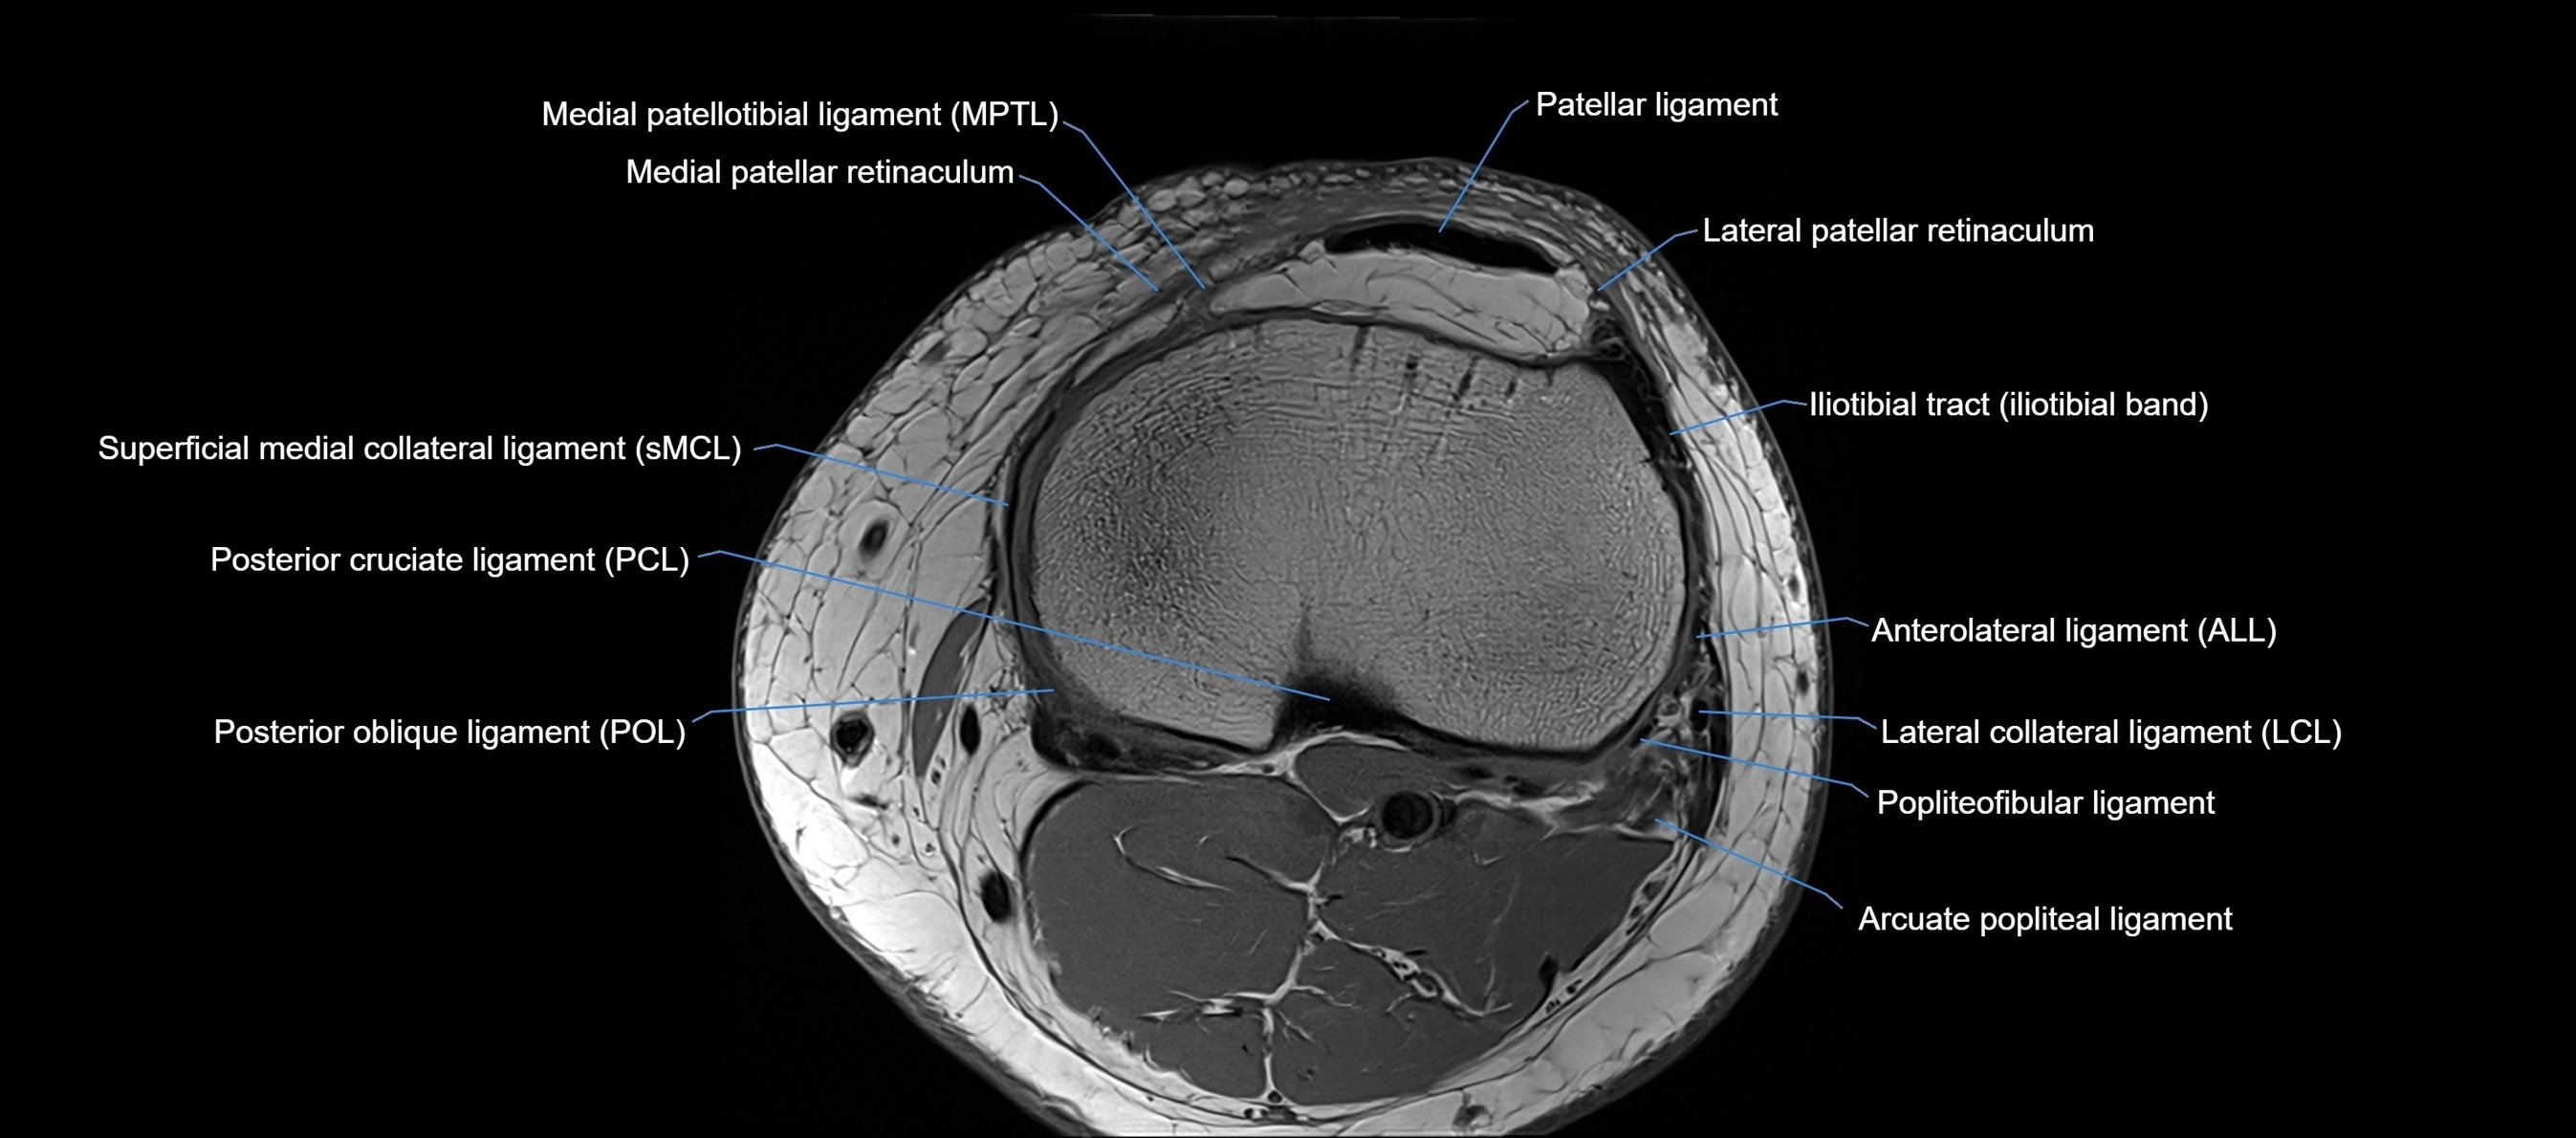

MRI images

image